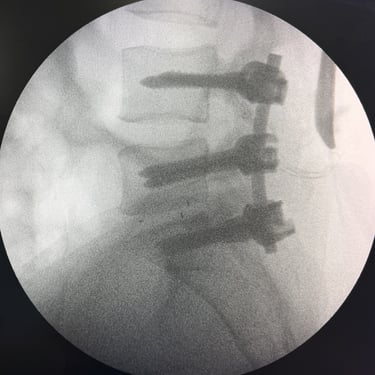

Manejo quirúrgico de la hernia lumbar con inestabilidad: enfoque moderno con FTP y TLIF

La hernia lumbar con inestabilidad vertebral es una patología frecuente que causa dolor lumbar persistente, ciática y limitación funcional, afectando la calidad de vida del paciente. Cuando el tratamiento conservador no logra resultados adecuados, la cirugía se convierte en la mejor opción terapéutica. La fijación transpedicular con tornillos (FTP) junto con la técnica TLIF (Transforaminal Lumbar Interbody Fusion) permite estabilizar la columna, descomprimir las estructuras nerviosas y lograr una adecuada fusión ósea. Este abordaje, especialmente mediante técnicas mínimamente invasivas (MISS), ofrece múltiples beneficios, como menor daño muscular, menor dolor postoperatorio y recuperación más rápida, facilitando el retorno temprano a las actividades cotidianas con mejores resultados clínicos.